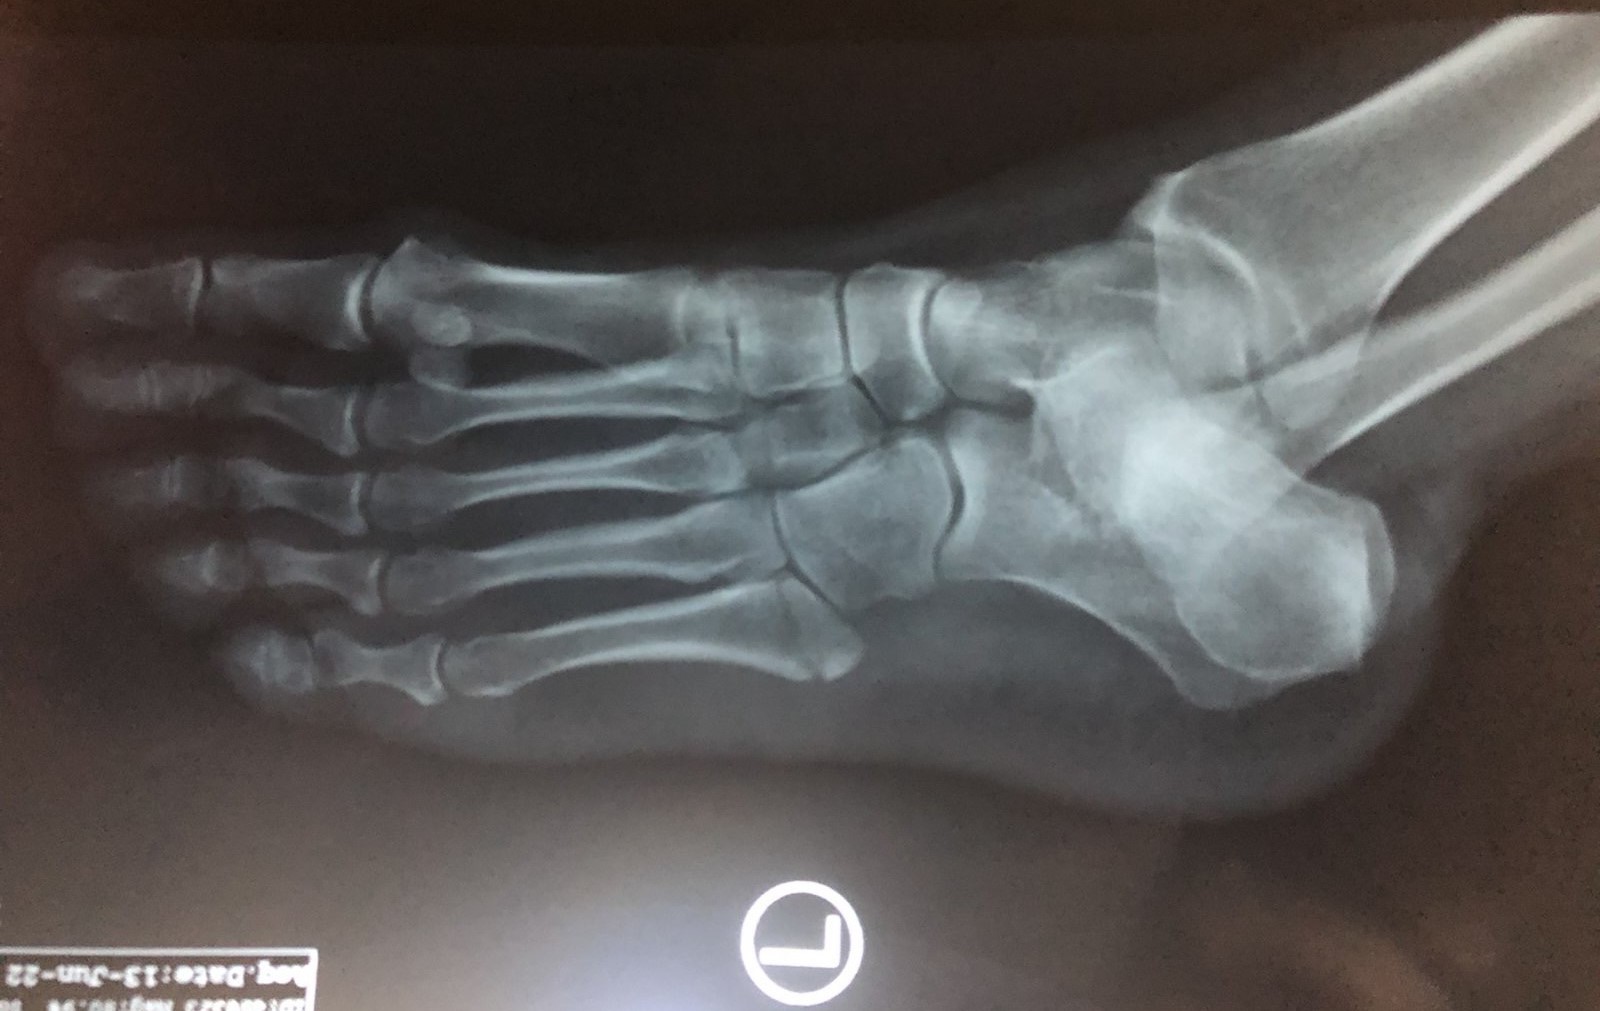

Όπως σε κάθε τραυματισμό, η επίσκεψη σε έναν έμπειρο Ορθοπαιδικό είναι απαραίτητη. Αρχικά, ο ιατρός λαμβάνει το ιστορικό του ασθενούς και στη συνέχεια προχωρά στην κλινική εξέτασή του. Στην συνέχεια, μια απλή ακτινγραφία είναι συνήθως αρκετή για τη διάγνωση του κατάγματος. Υπάρχουν όμως και περιπτώσεις όπου για τον εντοπισμό του κατάγματος Jones μπορεί να είναι απαραίτητη η διενέργεια αξονικής ή μαγνητικής τομογραφίας.